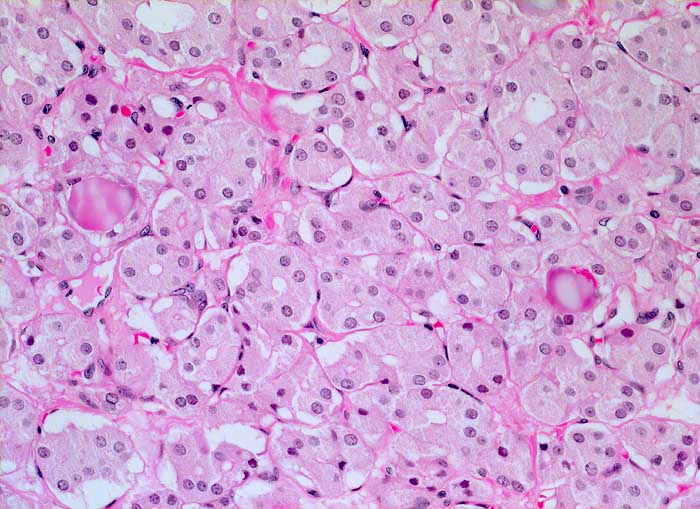

Einleitung

Punktate aus mikrofollikulären oder trabekulären Adenomen sind zellreich und kolloidarm. Die Thyreozyten bilden oft Mikrofollikel oder kleine Rosetten, die eosinophile Kolloidtropfen umschliessen. Die Kerne sind gleichförmig rund, fein granuliert und zeigen keine Atypien. Gelegentlich finden sich regressive Veränderungen. Zytologisch sind follikuläre Adenome und hoch differenzierte follikuläre Karzinome nur schwer zu unterscheiden. Aus diesem Grund werden beide Läsionen mit dem Begriff "follikuläre Neoplasie" bezeichnet. Unten sind zwei Beispiele von mikrofollikulären Adenomen abgebildet.